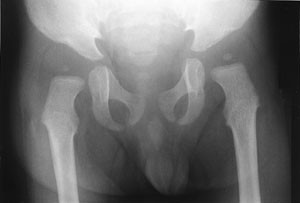

Pasienten ble så 13 måneder gammel innlagt i barneavdeling i forbindelse med ny feberepisode. Ved innleggelsen var han dystrofisk, med stor abdomen, tynne ekstremiteter og slunkne nates. Noe grove ansiktstrekk ble bemerket, men gav ikke umiddelbart videre assosiasjoner. Utredning av malabsorpsjon med tanke på cøliaki ble startet. Metabolsk screening av urin og serum ble rekvirert. Røntgen thorax viste klare lunger og et normalt stort hjerte, men påfallende brede costae (fig 1). Fysioterapeutisk vurdering bemerket en forsinket motorisk utvikling og stive ledd. Øre-nese-hals-undersøkelse viste betydelig nasalstenose og hypertrofiske tonsiller. Foreldrene kunne fortelle om uttalt pustebesvær og sterk snorking om natten, med tendens til pustestopp. Primær malabsorpsjon og cøliaki ble utelukket med serologiske prøver. Ultralyd abdomen viste leverstørrelse i øvre normalområde.

Omfattende radiologisk utredning ble rekvirert. Røntgen av kraniet viste et relativt stort nevrokranium (fig 2) med sannsynlig fortykket calvarium i basale deler. Røntgen av columna viste en kyfotisk knekk på torakolumbalovergangen (fig 3). Røntgen av bekken viste dysplastiske hofter bilateralt (fig 4). Røntgen av håndledd viste forandring av metakarpene. Røntgenologenes endelige konklusjon var dysostosis multiplex, forenlig med Hurlers syndrom. Undersøkelse hos øyelege styrket denne mistanken ytterligere, da det ble funnet bilateral, diffus tilsløring av hornhinnene. Plastisk kirurg bekreftet at det forelå triggerfinger på høyre hånds 4. finger, et typisk funn ved Hurlers syndrom.